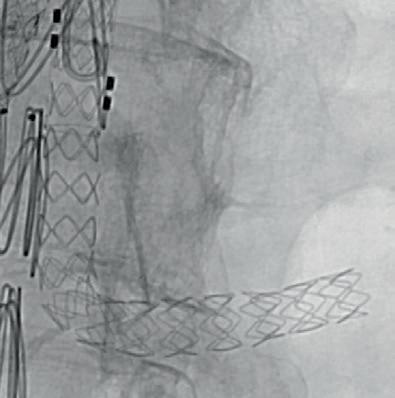

First official ESVS consensus statement consolidates expert opinion on “truly novel” aTEVAR procedure

an ageing population and increasing demand for complex endovascular aortic solutions, Santi Trimarchi (Fondazione IRCCS Cà Granda Ospedale Maggiore Policlinico, Milan, Italy) and a global team of experts recently authored a consensus statement on ascending thoracic endovascular aortic repair (aTEVAR).

The aTEVAR statement includes recommendations on patient selection, procedural strategies, and postoperative management among other areas.

“By addressing key topics such as landing zones, stent graft sizing, risk assessment, and adjunctive procedures, this document aims to guide clinical practice, improve patient outcomes, and enhance procedural safety,” Trimarchi and colleagues write in the paper.

Continued from page 1

speaking to Vascular News following the open-access publication of the statement in EJVES, notes a growing interest in this niche area. “The data are limited, but the observational evidence we do have shows that a large number of aortic lesions are being treated with aTEVAR,” he says. Trimarchi also highlights growing interest in aTEVAR from industry.

Behind these factors, Trimarchi continues, is an ageing population in need of new aortic technologies.

“Twenty years ago, the mean age of patients who had a type A dissection was about 70, 72 years of age; now, it’s shifting towards 80,” he points out. Trimarchi adds that with age comes fragility and that aTEVAR “offers these patients a chance”.

“Our aim was to try to give a framework to a topic that many people are discussing, and it was a chance to highlight the state of the art and figure out how we can move forward,” Trimarchi summarises.

A lack of evidence, however, necessitates caution. This is a point stressed by Twine and Jonathan R Boyle (University of Cambridge and Cambridge University Hospitals NHS Trust, Cambridge, UK) in an editorial accompanying Trimarchi and colleagues’ paper in EJVES. Speaking to Vascular News, Twine emphasises the “truly novel” nature of aTEVAR and the fact that “very few units are doing it at the moment”. With this in mind, he stresses the importance of “trying to harmonise” all aspects of care around the procedure and avoid “outlying practice” at this stage—which the consensus statement aims to achieve. “I hope the document reinforces that you can’t start doing these very difficult, novel procedures in isolation,”

AORTIC

Twine remarks, stressing that “there needs to be an experienced multidisciplinary team in place, careful patient selection and consent and ideally the use of a framework for implementation of new procedures.”